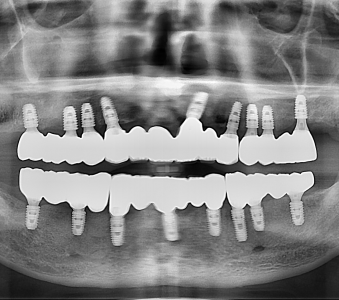

오스템 임플란트 프리미엄 BA 등급 사용

같은 오스템이라도 등급이 다릅니다. 더 빠른 골유착을 위해 프리미엄 등급을 사용합니다.

정확성 높은 치료의 시작 디지털 정밀진단 시스템

3D 디지털 데이터 기반으로 정확성 높고 정교한 치료가 가능합니다.

결과로 증명합니다.

국제모아치과의

실제 임상 증례